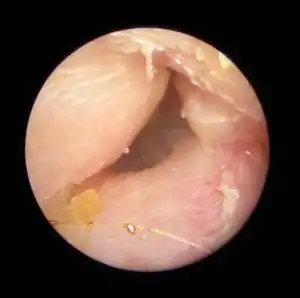

| Exostoses in the ear canal, as seen through otoscopy | |

Irritation from cold wind and water exposure causes the bone surrounding the ear canal to develop lumps of new bony growth which constrict the ear canal. Where the ear canal is actually blocked by this condition, water and wax can become trapped and give rise to infection. The condition is so named due to its prevalence among cold water surfers. Warm water surfers are also at risk for exostosis due to the evaporative cooling caused by wind and the presence of water in the ear canal.

The normal ear canal is approximately 7 mm in diameter and has a volume of approximately 0.8 ml (approximately one-sixth of a teaspoon).[4] As the condition progresses, the diameter narrows and can even close completely if untreated, although sufferers generally seek help once the passage has constricted to 0.5-2 mm due to the noticeable hearing impairment. While not necessarily harmful in and of itself, constriction of the ear canal from these growths can trap debris, leading to painful and difficult to treat infections.